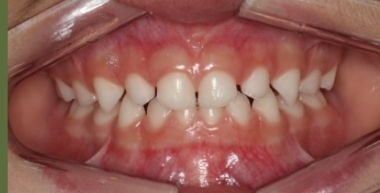

O tratamento que tem como objetivo tratar a má-oclusão através de recursos terapêuticos (aparelhos removíveis) que utilizam estímulos funcionais precocemente através de orientação mastigatória, desgaste seletivo, acréscimo às superfícies dentárias.